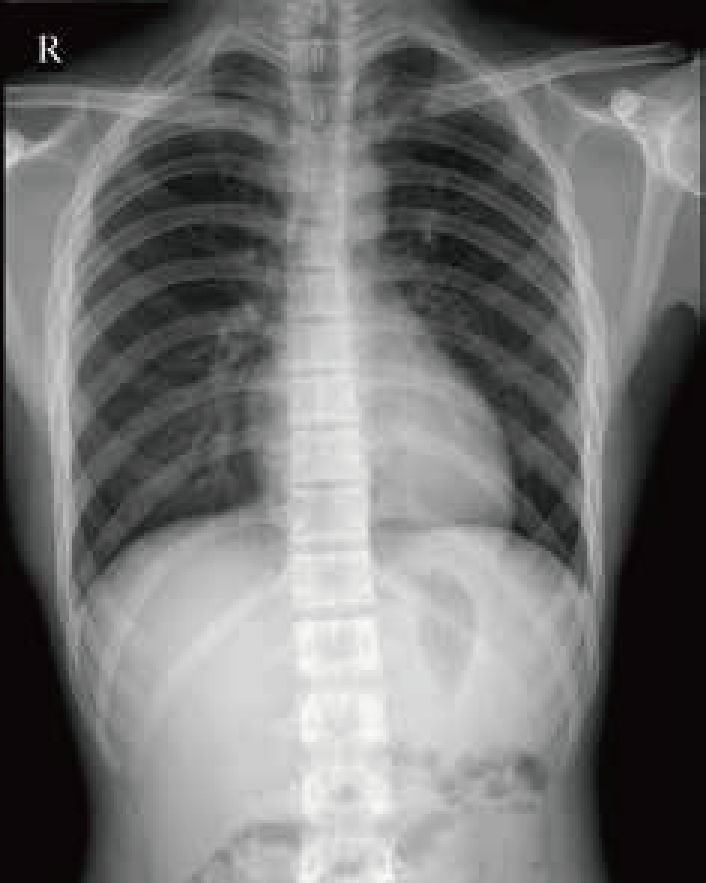

臨 床 圖 集